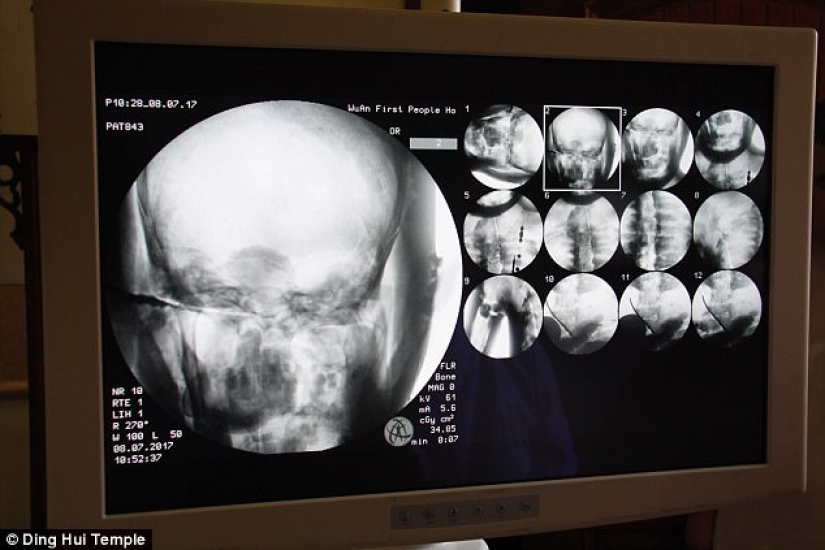

By Pictolic https://www.pictolic.com/article/a-thousand-year-old-mummy-of-a-buddhist-monk-has-a-brain-and-skeleton-preserved-in-perfect-condition.htmlThe mummified body of a thousand-year-old Buddhist monk still has the bones and brain intact. This was revealed by a CT scan.

The CT scan was performed on July 8. People were shocked when the doctors said that Ci Xian's skeleton and brain were in perfect condition. "We can see that his bones are as healthy as a normal person's. The upper jaw, upper teeth, ribs, spine, and all joints are perfectly preserved. This is incredible, " said Dr. Wu Yongqing.